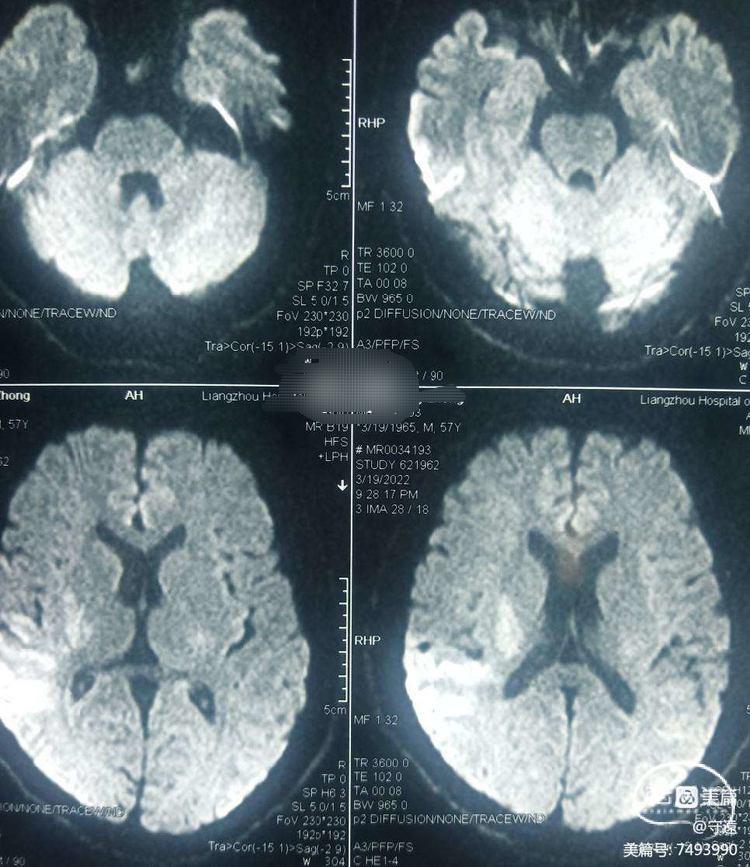

CT无出血,核磁共振:DWⅠ显示右侧颞枕顶大片状高密度。考虑为大血管闭塞(心源性血栓可能)。

静脉溶栓:给予阿替普酶63.5mg溶栓。继之血管内介入支架取栓治疗。

造影显示:左侧大脑中动脉分叉部闭塞。